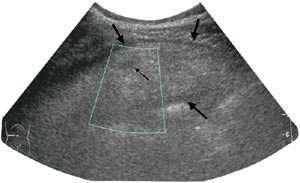

Pasient 1. En 56 år gammel mann med medikamentelt behandlet hypertensjon og tidligere operert brokk i epigastriet ble henvist fra primærlege til ultralydundersøkelse av abdomen på grunn av smerter under venstre costalbue, tiltakende over en uke og konstante de siste tre dager. Undersøkelsen viste en ekkorik, hovedsakelig homogen, 12 x 3 cm stor oval masse med enkelte lavekkogene avsnitt i sentrale deler og et tynt hypoekkoisk sjikt omkring (fig 1). Supplerende CT viste en 10 x 3 cm stor oppfylling i det tilsvarende området under venstre costalbue. Den lå tett an mot bukveggen foran ventrikkelen og hadde attenuasjon som fettvev med ødem (fig 2). Klinisk var han subfebril, direkte og indirekte øm medialt og nedenfor venstre costalbue, samt hadde forverring av smerten ved hoste. Man mistenkte omentnekrose, og pasienten ble operert ved laparoskopi. Alt nekrotisk vev ble resecert, og histologisk diagnose var fettvev med akutt hemoragisk infarkt og subserøs fibrose. Postoperativt forløp var ukomplisert.

Ultrasonografisk viser lesjonen seg som en rund eller oval ekkorik oppfylling lokalisert til ømhetens punctum maximum (1, 6) – (8). Oppfyllingen er ikke-komprimerbar og ofte adherent til peritoneum, sistnevnte demonstreres best i sagittalplan, hvor man under respirasjon kan observere lesjonens manglende bevegelighet i forhold til øvrig intraperitonealt innhold (7). Det ses ofte et 1 – 2 mm tynt, hypoekkoisk sjikt rundt oppfyllingen. Andre beskrevne assosierte funn er hypoekkoiske foci inni lesjonen som sannsynligvis representerer hemoragiske forandringer, fortykkelse av tilgrensende tarmvegg og peritoneum og masseeffekt med dislokasjon av tarm. Ved bruk av fargedoppler ses manglende blodstrøm.